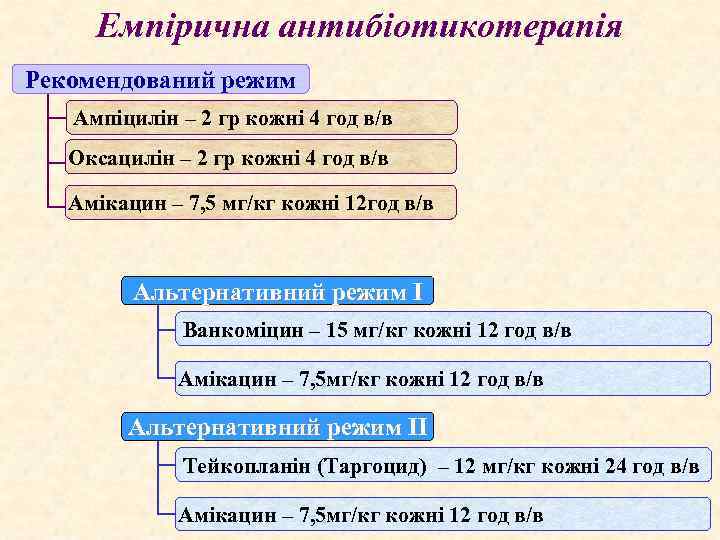

Емпірична антибіотикотерапія Рекомендований режим Ампіцилін – 2 гр кожні 4 год в/в Оксацилін – 2 гр кожні 4 год в/в Амікацин – 7, 5 мг/кг кожні 12 год в/в Альтернативний режим I Ванкоміцин – 15 мг/кг кожні 12 год в/в Амікацин – 7, 5 мг/кг кожні 12 год в/в Альтернативний режим II Тейкопланін (Таргоцид) – 12 мг/кг кожні 24 год в/в Амікацин – 7, 5 мг/кг кожні 12 год в/в